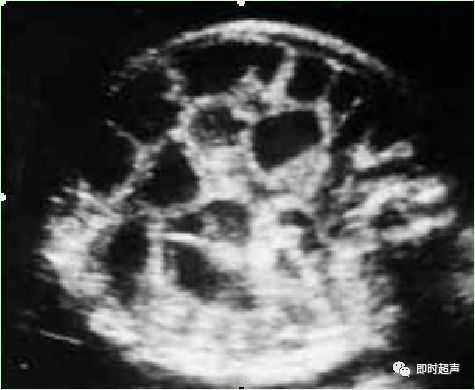

七、肠管回声增强(EB)

超声显示:胎儿肠管强回声是指胎儿肠管回声强度接近或高于其周围骨骼回声的强度。常见于中期妊娠胎儿的小肠及足月妊娠胎儿的结肠,是产前诊断的指征之一。中孕期的超声检出率为 0.1% ~ 1.8%。

孕期发现胎儿肠管强回声,除考虑染色体异常可能外,尚需排除其他异常,如宫内感染、 巨细胞病毒感染 、出血、纤维囊泡症、小肠闭锁、胎粪性的肠梗阻及地中海贫血等。

肠穿孔钙化